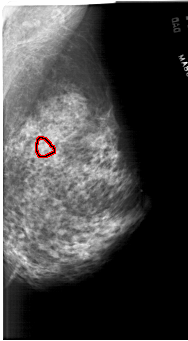

FILE: A_1762_1.RIGHT_CC.OVERLAY

TOTAL_ABNORMALITIES 1

ABNORMALITY 1

LESION_TYPE CALCIFICATION TYPE PLEOMORPHIC DISTRIBUTION CLUSTERED

ASSESSMENT 4

SUBTLETY 2

PATHOLOGY BENIGN

TOTAL_OUTLINES 1

BOUNDARY